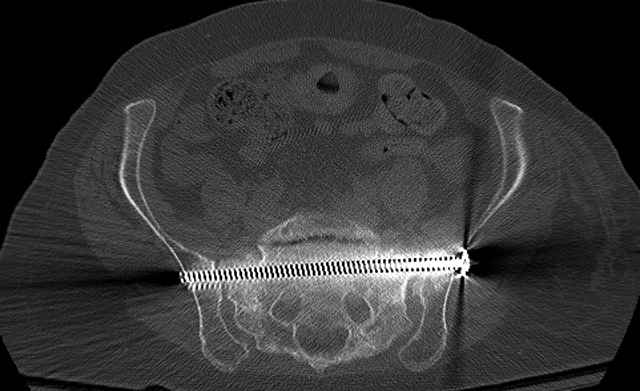

Pelvic CT Scan - 3 Months After Fall

Ramus Fractures

Percutaneous Fixation

(B) Ramus-Retrograde

2 TransIliac-TransSacral

Upper Segment